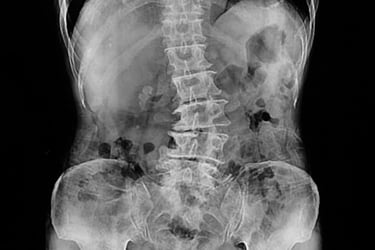

La escoliosis es una condición en la que la columna vertebral se curva de manera anormal, a menudo formando una "S" o una "C" en lugar de estar recta. Aunque algunos casos de escoliosis son leves y no causan problemas significativos, otros pueden generar dolor, incomodidad e incluso dificultar el movimiento y la postura. Comprender los síntomas, las causas y los tratamientos disponibles para la escoliosis es esencial para gestionar esta condición y mejorar la calidad de vida.

La escoliosis es una condición caracterizada por una curva anormal en la columna vertebral, que puede ocurrir a cualquier edad, pero se diagnostica comúnmente durante la niñez o la adolescencia. La curvatura puede variar desde leve hasta severa y generalmente se desarrolla a medida que la columna crece. En algunos casos, la escoliosis puede empeorar con el tiempo, lo que provoca más incomodidad, restricción de movimiento y, en casos graves, problemas respiratorios.

Aunque la causa exacta de la escoliosis generalmente se desconoce (escoliosis idiopática), existen varios tipos y causas conocidas, que incluyen: